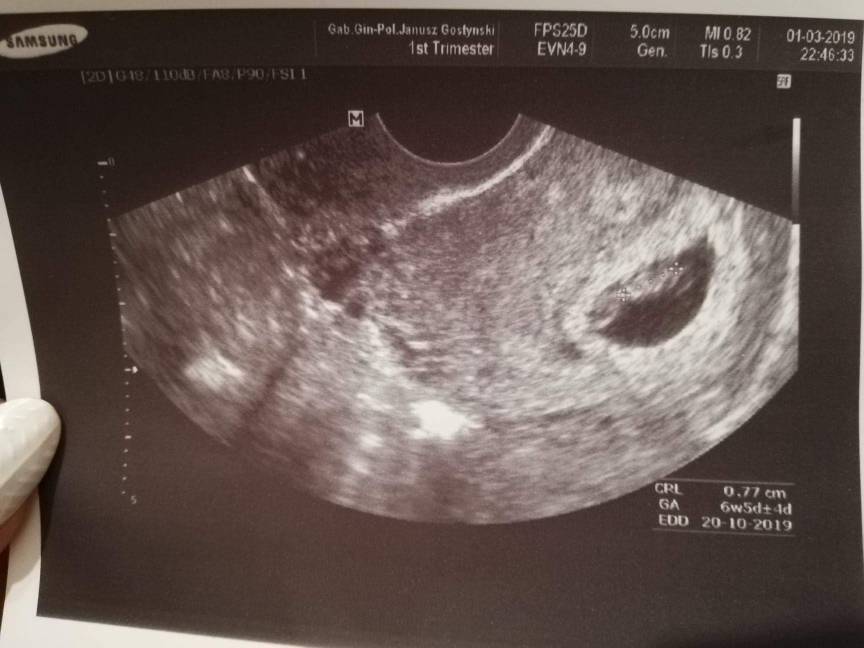

SuperTo za okolo 9 dni juz bedzie zarodek. U mnie 5+6 wygladalo tak jak na pierwszym foto.

A 6+5 jak na drugim i tu juz byla akcja serduszka.Zobacz załącznik 973845Zobacz załącznik 973847